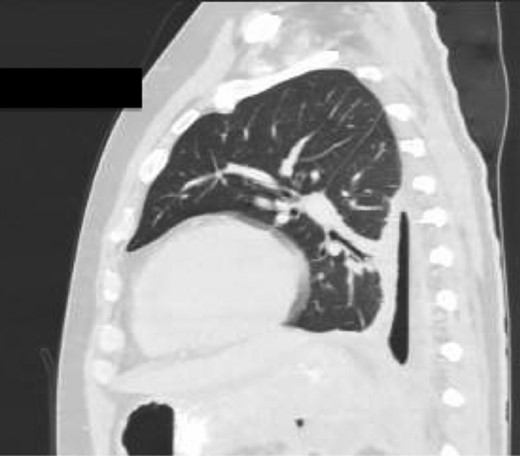

An Intercostal drain was inserted under CT-guidance aiming to decompress the pleural space. Amylase level in the pleural drainage was 880 U/l, Lipase 472 U/l. There was significant reduction of the Hydropneumothorax (Fig. 5). Given his young age, potential for loss of lung volume and infection he proceeded to decortication.

Sagittal view CT Chest post-intercostal catheter drainage of the Pancreatico-pleural fistula. Smaller residual space can be noted compared to Image 3, with some ongoing loss of lung volume and small fluid collection.